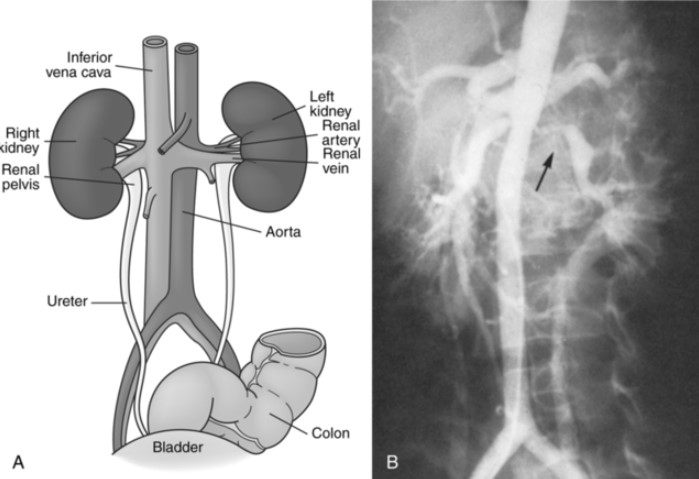

Kidneys - Abdominal ultrasound and computed tomography (CT) scan; magnetic resonance imaging (MRI); aortography; and selective renal angiography are common tests, coupled with palpation.